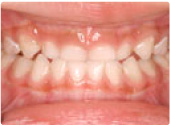

ムーシールドによる小児の矯正

治療前

治療後

この症例は、乳歯列(5歳)の受け口を「ムーシールド」という就寝中に使う矯正装置を使用して治療しました。受け口のままでいると、永久歯に生え変わったときにも受け口になりやすいです。 乳歯列の時から出来ることを積極的にすると、成人になって矯正をしなくてすむ確率も上がります。